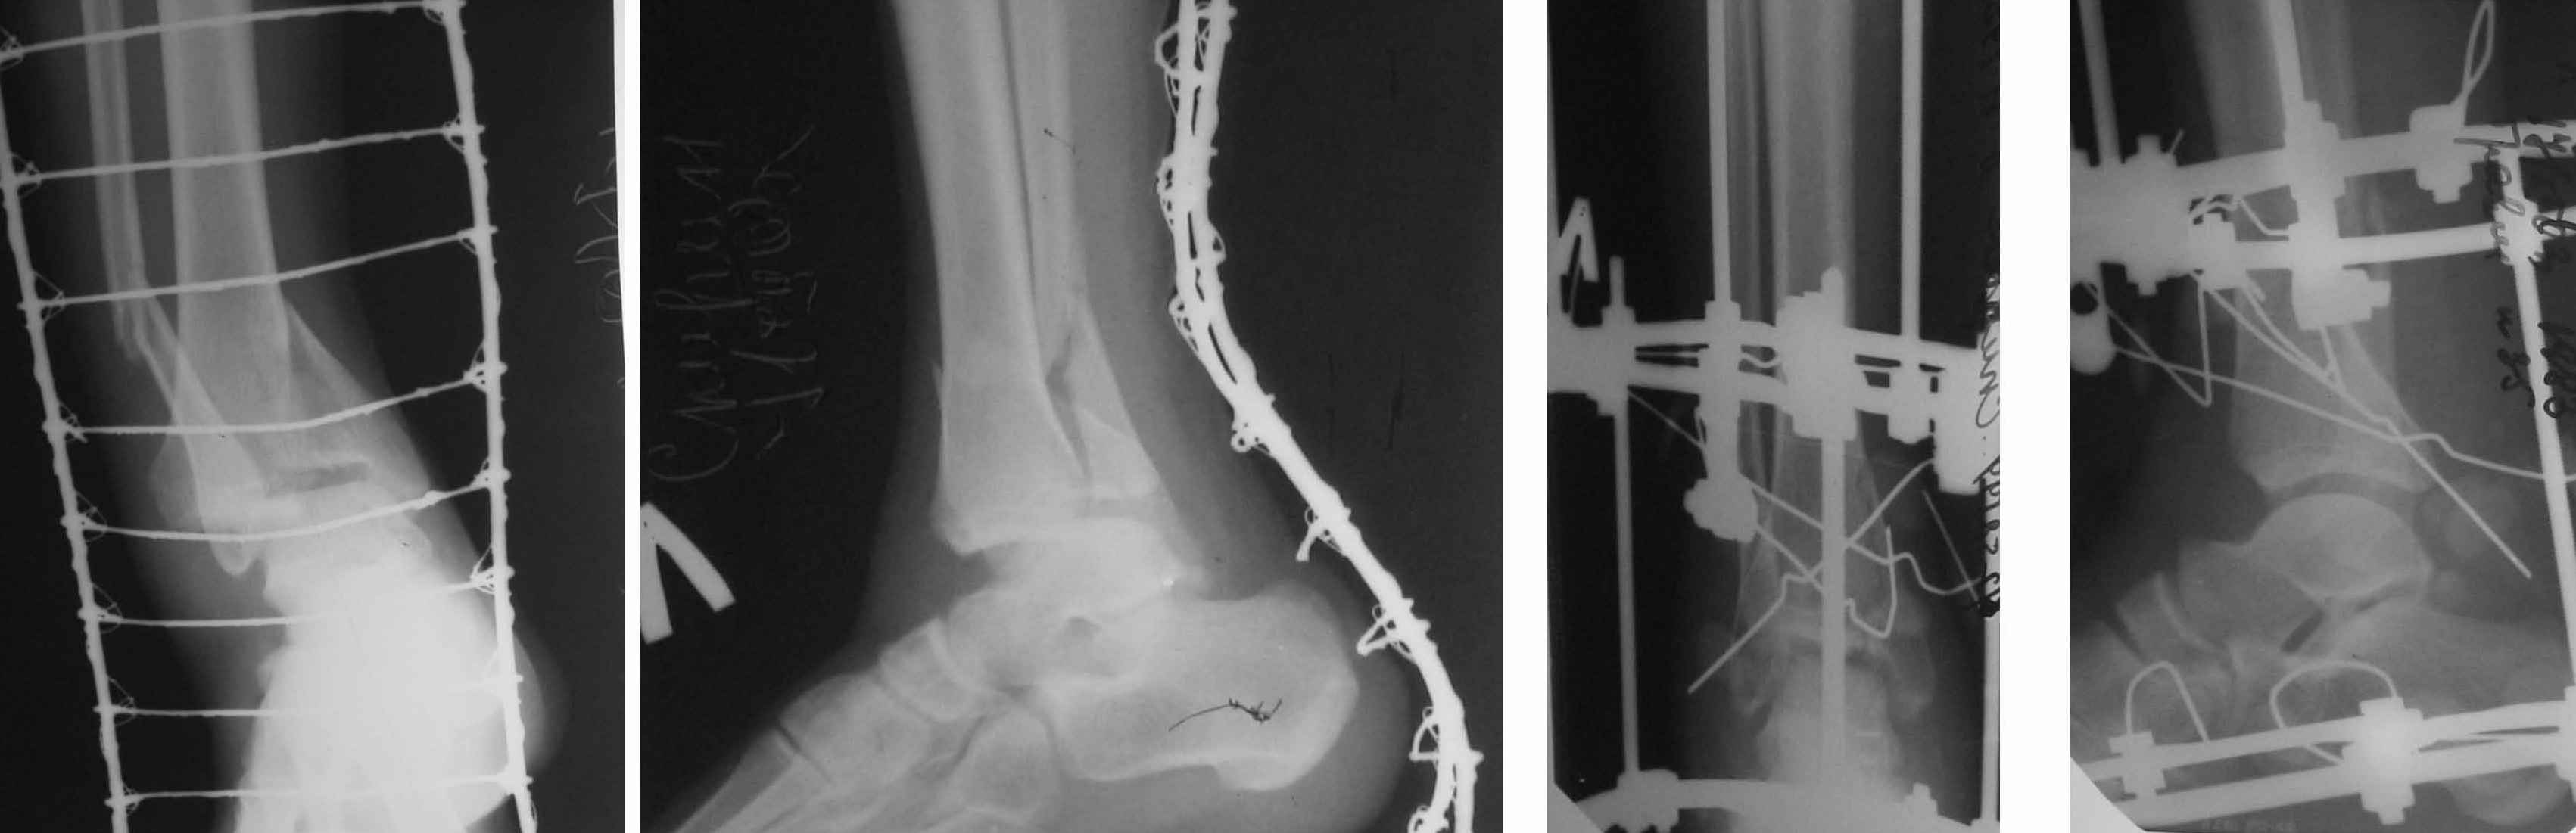

1. Ilizarov frame as definitive managment (it is crucial to perform high-quality about ankle fixation for early distal ring removing and ROM restoration) - see photo.

I've sent you picture of the leg. I have problem with this patients because he has had dyspnoea, hemoptysis. We have made, ABG, X-Ray, etc and finally angio-CT of thorax. Our diagnosis is fat embolus syndrome with some kind of acute lung injury (moderate hypoxia)

Now, he has had 3rd debridement in medial part of the leg, but his problem is also in lateral part - Morel - Lavalle Lesion...

In Friday I hope to stabilize ankle fracture. And then I plane to make acute shortening after remove all necrotic tissue from lateral and posterior compartment.